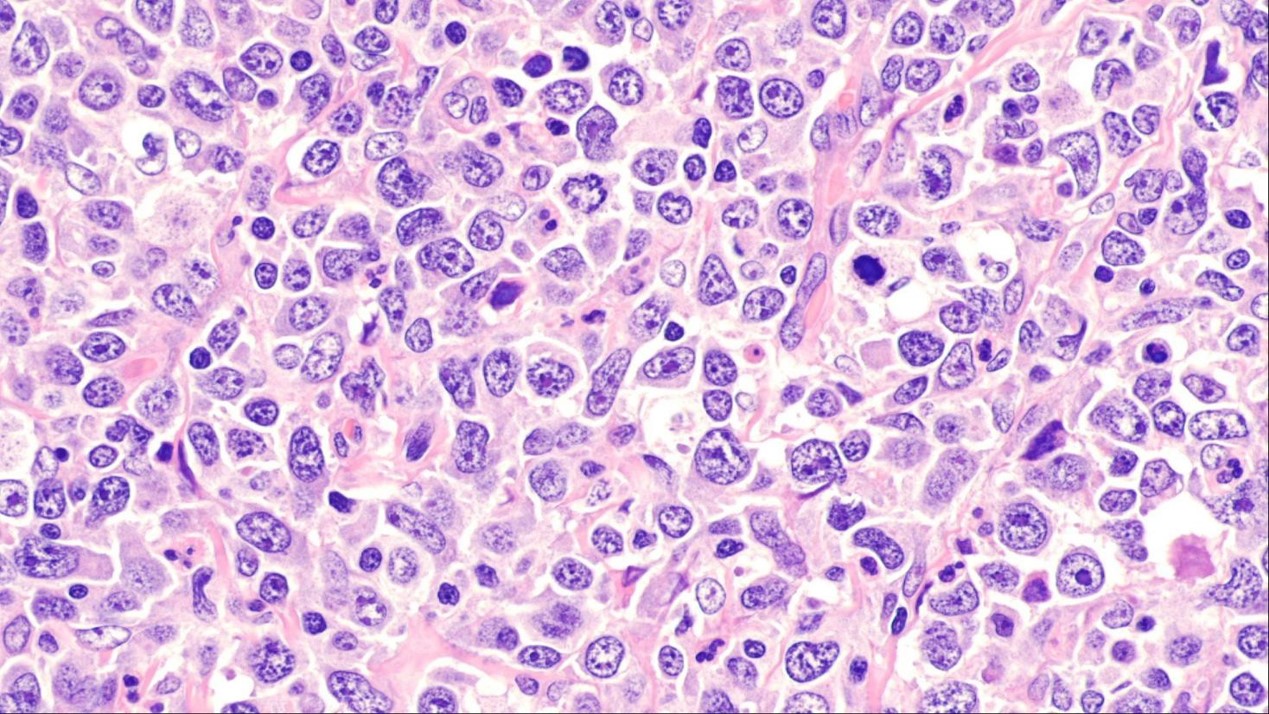

Lymphoma is a type of blood cancer that affects white blood cells called lymphocytes. There are many different types of lymphoma, but this latest breakthrough is in a type called diffuse large B-cell lymphoma (DLBCL), which affects our B cells. When operating normally, B cells help to fight infection in the body.

Within DLBCL, the researchers have now discovered a new subtype named 'Mann-type DLBCL'.

The researchers found that Mann-type DLBCL lymphoma cells always carry this sugar and are not sensitive to conventional anti-cancer drugs. Mannose is found naturally on the surface of many infective agents like viruses, but is typically not abundant on normal human cells.

The sugar's presence helps the cancer cells to survive and grow more quickly, making them resistant to standard treatments - eventually resulting in an aggressive form of cancer and poorer outcomes for patients.